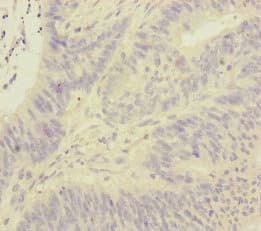

Rabbit Polyclonal FOXRED1 antibody. Suitable for WB, IHC-P and reacts with Human samples. Immunogen corresponding to Recombinant Fragment Protein within Human FOXRED1 aa 300 to C-terminus.

Applications IHC-P, WB